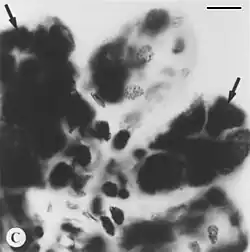

Der Nachweis nach Feulgen und Rossenbeck, oder kurz die Feulgenreaktion, ist eine von Joachim Wilhelm Robert Feulgen 1924 mitentwickelte histochemische Methode zum Nachweis von Desoxyribonukleinsäure (DNA). Zunächst wird in der zu analysierenden Probe (Gewebeprobe, Probe von Mikroorganismen) die DNA durch Salzsäure hydrolysiert, wobei die Molekülverbindungen von Base und Zucker getrennt werden. Es entstehen freie Aldehydgruppen. Die Aldehyde ergeben mit fuchsinschwefliger Säure (Schiffs Reagenz) eine rotviolette Färbung.[1] Eine Erkennung dieser DNA-Reste ist nun unter dem Mikroskop möglich. Optional kann mit Lichtgrün SF gegengefärbt werden.